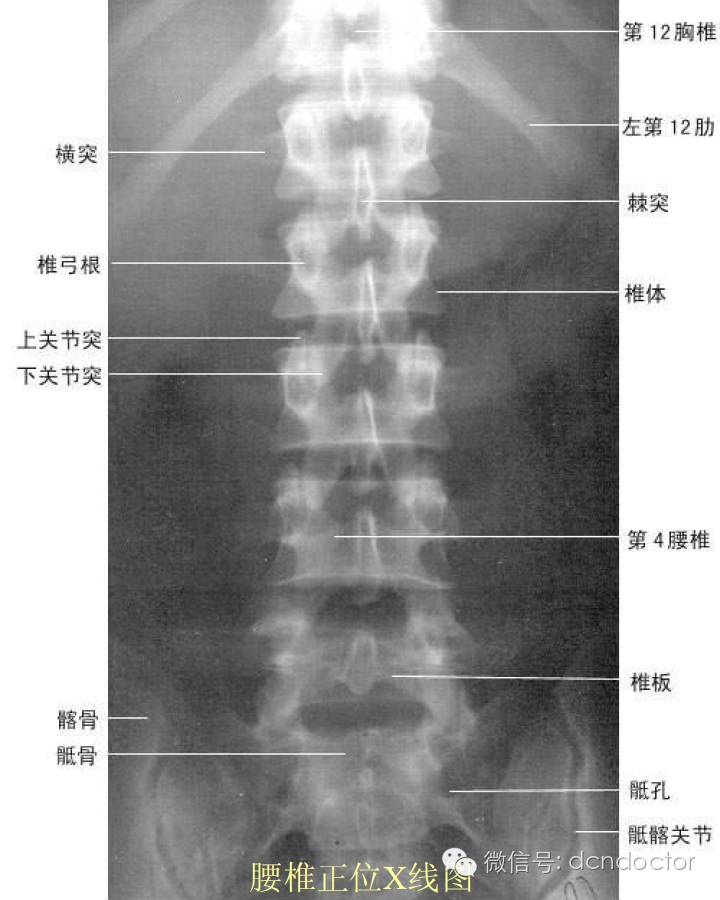

对于腰椎骨折,错位,骨质增生, x光片是最直接的诊断方法.

骨质增生x光片图解

腰椎骨质增生片子图片

骨质增生图解